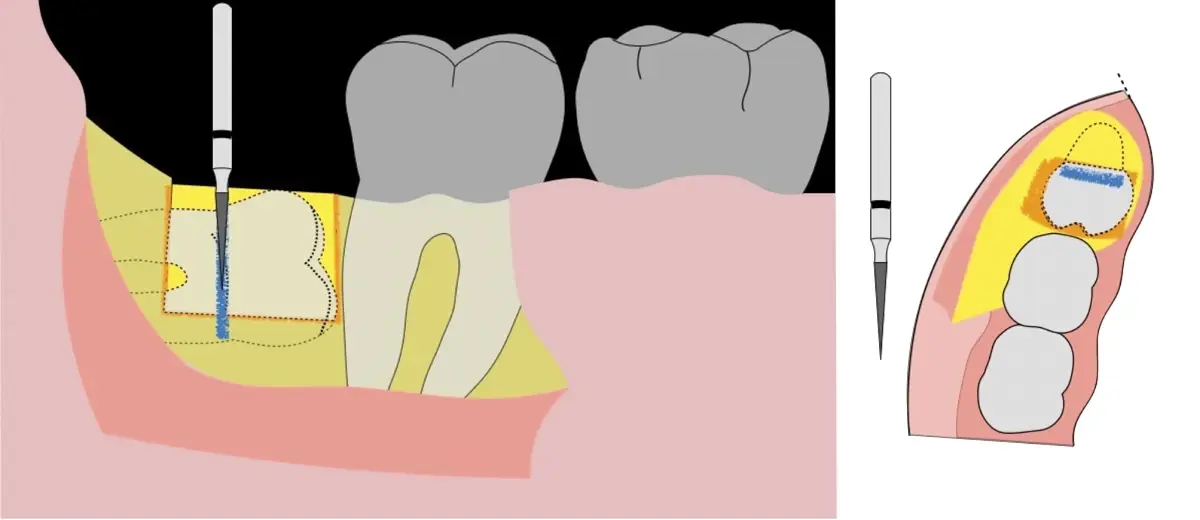

Figura 8. Odontosección mediante fresa de alta rotación y/o inserto de corte de piezoeléctrico. Posteriormente se procede al ensanchamiento del espacio pericoronario con el periótomo de piezoeléctrico para facilitar la avulsión de la pieza dentaria.

Figura 9. Avulsión de la parte coronaria de la tercera molar.

Figura 10. Tracción mesial del remanente dentario utilizando botadores en bandera.

Figura 11. Avulsión del remanente radicular de la tercera molar.